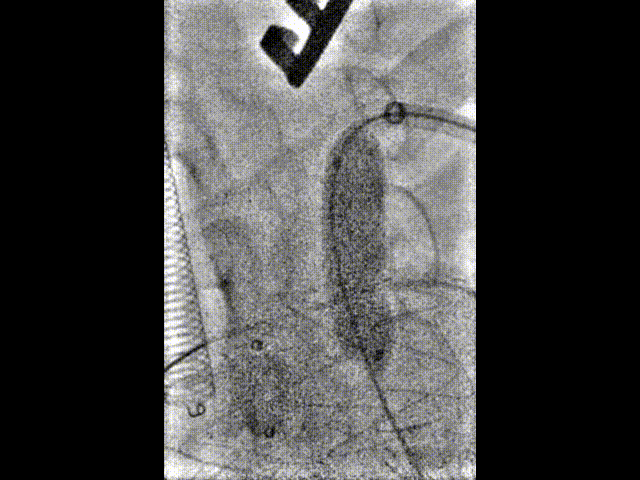

★ 术后造影

支架释放完毕后,分别进行左前斜和右前斜造影。结果显示,支架形态良好,左侧颈总动脉和左锁骨下动脉分支血流通畅。右前斜位可见假性动脉瘤封闭完全,仅有少量内漏,考虑与膜渗相关。同时行颅内动脉造影,结果显示双侧颈动脉、双侧椎动脉以及颅内血管显影良好。结果表明,手术成功实现血管重建,假性动脉瘤有效封堵,且未对脑部供血造成不良影响。